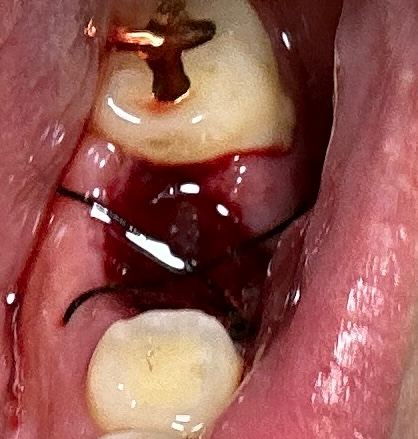

오늘 발치했는데요 양치는 어떻게하나요?

이를 뺀 자리에 검은 실처럼 묶여있네요

• 1번 째 사진